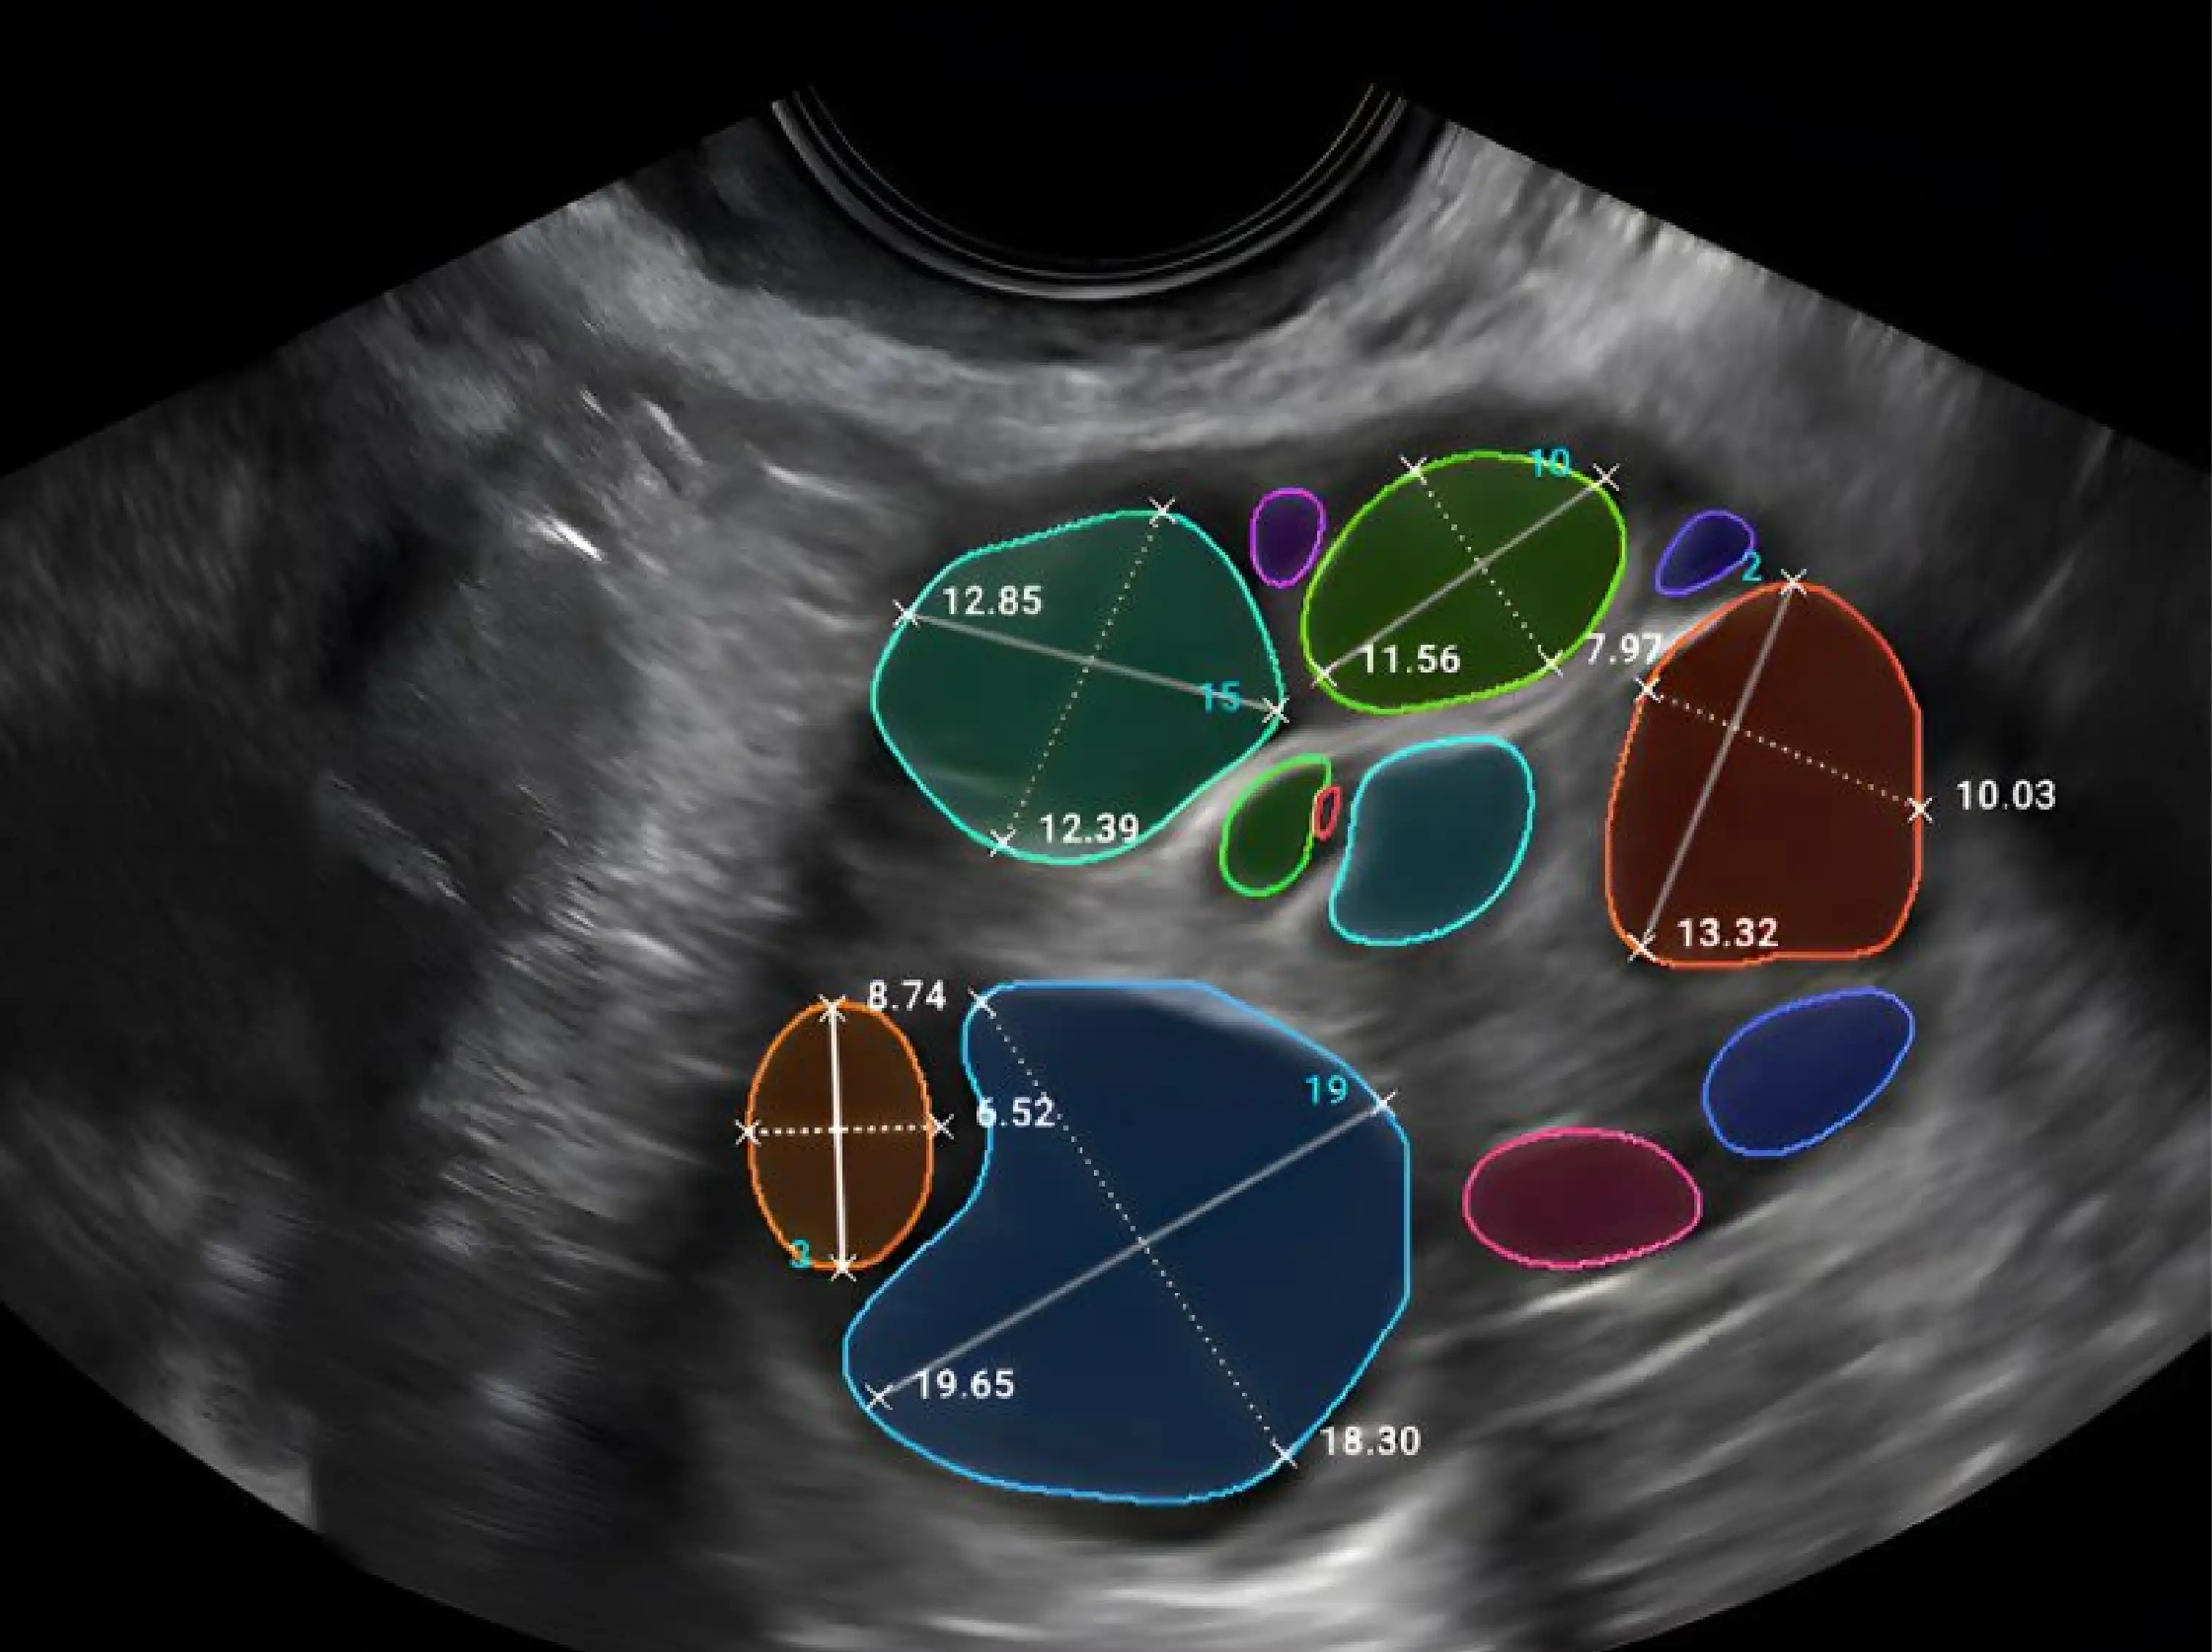

We strive to provide IVF centers and labs with high-quality equipment for the whole lab such as long-term embryo incubators, Assisted Reproductive Technology (ART) workstations, anti-vibration tables, and time- lapse incubators, clinical lasers, ICSI & IMSI station manipulators, consumables and portables.